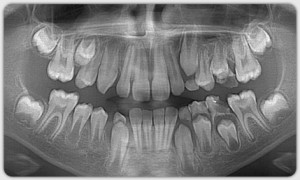

Ортопантомограмма и боковая телерентгенограмма